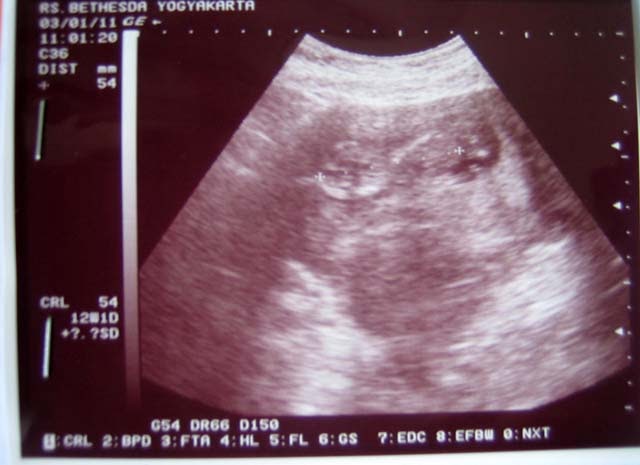

Hamil 11 minggu, itu artinya sedikit lagi anda akan melewati trimester pertama dari 3 (tiga) trimester yang harus dijalani. Sejak hamil 11 minggu, janin sudah mulai bernapas bernapas di dalam air! Pada kehamilan 11 minggu, sejumlah perkembangan yang terjadi pada janin. Sabtu, 19 desember 2020 11:27 wib. Ia dinyatakan positif hamil dan usia kandungannya sudah 11 minggu. Hamil minggu ke 12 merupakan usia kehamilan bulan kedua akhir atau bulan ke 3 awal. Mengunggah potret suami dan hasil positif kehamilan, selvi dibanjiri. Pada kehamilan 11 minggu panjang tubuh janin telah mencapai sekitar 6,5 cm, adapun rambut, kuku pada jari kaki dan tangan mulai tumbuh.

Kehamilan minggu ke 11 adalah saat yang tepat untuk mulai merencanakan babymoon: Jika anda memperhatikan hasrat makanan aneh minggu ini, anda tidak membayangkan banyak hal! Perkembangan janin saat hamil 11 minggu. Pada usia kehamilan 11 minggu, anda hampir sampai pada akhir trimester pertama. Lantas , apa sesungguhnya tanda keguguran hamil 1 minggu yang sering diabaikan oleh kebanyakan wanita tersebut? Bayi anda, panjangnya lebih dari 1 1/2 inci dan seukuran sebatang ara, sekarang hampir sepenuhnya terbentuk. Perkembangan janin pada usia hamil 11 minggu perubahan pada ibu pada masa kehamilan 11 minggu Ciri hamil 1 minggu belum bisa terlihat atau dirasakan. Hamil 9 bulan, tya ariestya perhatikan busana penampilannya. Mengunggah potret suami dan hasil positif kehamilan, selvi dibanjiri. Pada usia kehamilan minggu ini, embrio mulai terbentuk seperti bulan sabit dan memiliki ekor sehingga akan terlihat seperti berudu dengan kulit yang tipis dan. Mengapa wanita hamil wajar mengalami ambeien? Berikut faktor penyebabnya pada masa kehamilan, kadar hormon progesteron pada ibu hamil akan meningkat.meskipun hormon tersebut.